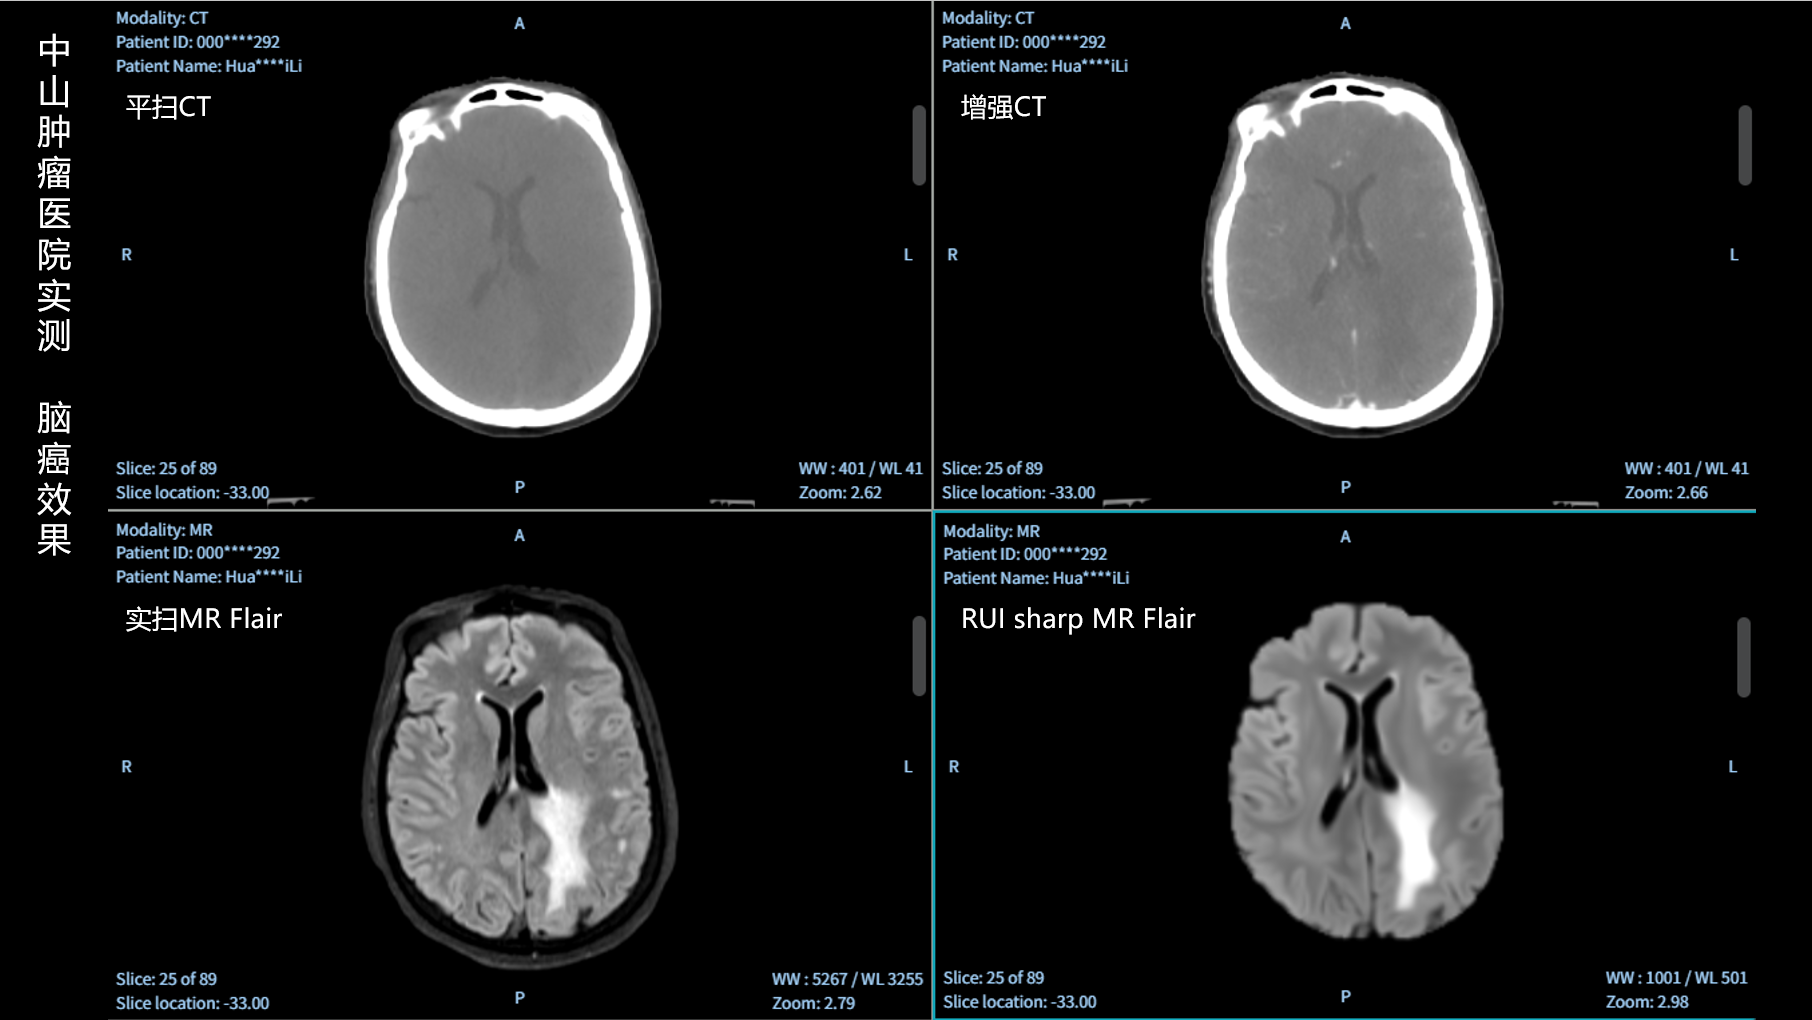

RUI sharp H(锐影)可在不依赖MRI的前提下,显著提升头部CT图像的软组织分辨率,为临床提供更高质量的辅助信息,尤其适用于MRI资源受限或较难配准的头颈部放疗感兴趣区勾画场景。

可大幅提高头部CT影像软组织分辨率,使肿瘤和周边器官显示更清晰,为放疗靶区勾画提供参考。

无需图像配准,CT和锐影图像同源,可匹配、叠加、"淡入淡出"显示。